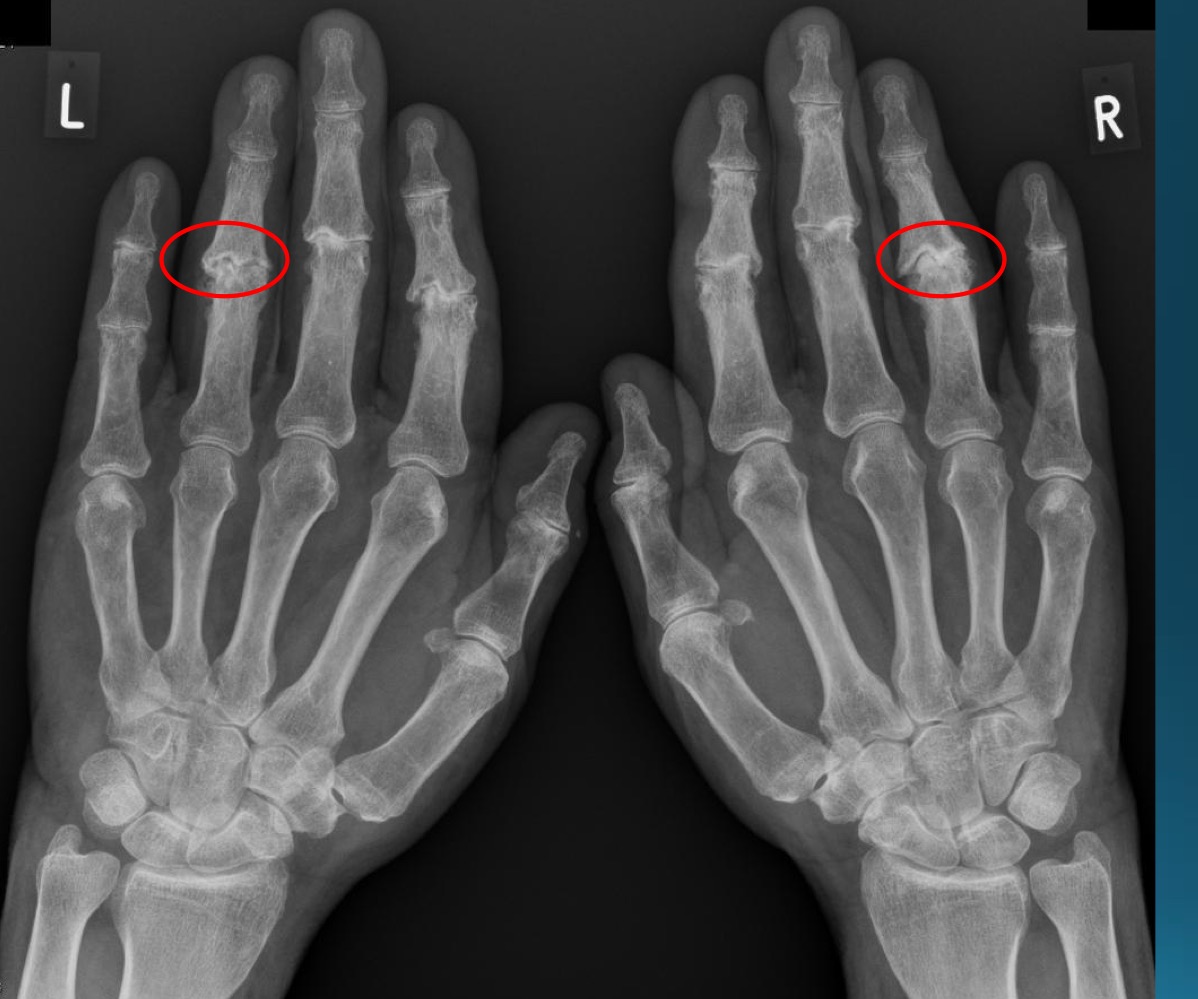

what are the findings in this image?

erosive osteoarthritis

waht are the features denoting erosive osteoarthritis on radiograph?

central erosions creating gull wing sign

EOA likes what joints?

DIP, PIP, 1st CMC

what referral should you make with EOA

rheumatologist